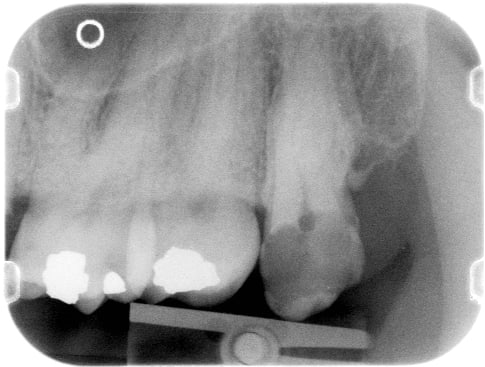

on voit qu'effectivement elle avait de belles hanches...

l'image est trompeuse, on voit le palais osseux en perspective mais le trait vertical d'alvéolectomie juste en distal de 27 reflète la réalité clinique.

belle regularisation de crete osseuse, que tu ne peux même pas coter car faite au cours de la séance d'extraction.

Par contre, moi je vois sur tes radios, des amalgames, qui mériteraient eux aussi des avulsions, mais beaucoup plus conservatrices ;)

Vu les clichés elle semble accessible alors pourquoi pas: endo-ic-co avec une éventuelle élongation coron. ?